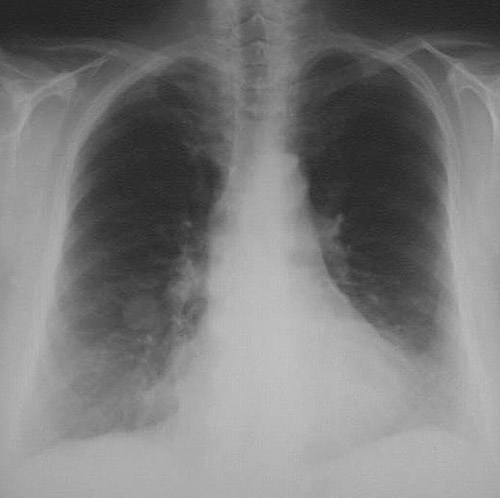

| Here is another PA chest radiograph with a very discrete, rounded "coin lesion" in the right lower lobe of the lung. This is a pulmonary hamartoma, an uncommon neoplasm that is composed of benign tissue elements such as cartilage, respiratory epithelium, and blood vessels that normally occur in lung. There may be calcifications. |